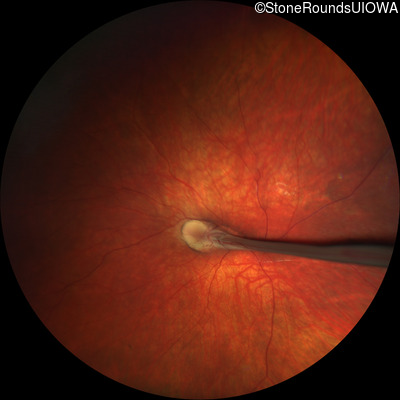

Fundus Photography - Right - 10/300

Exemplar